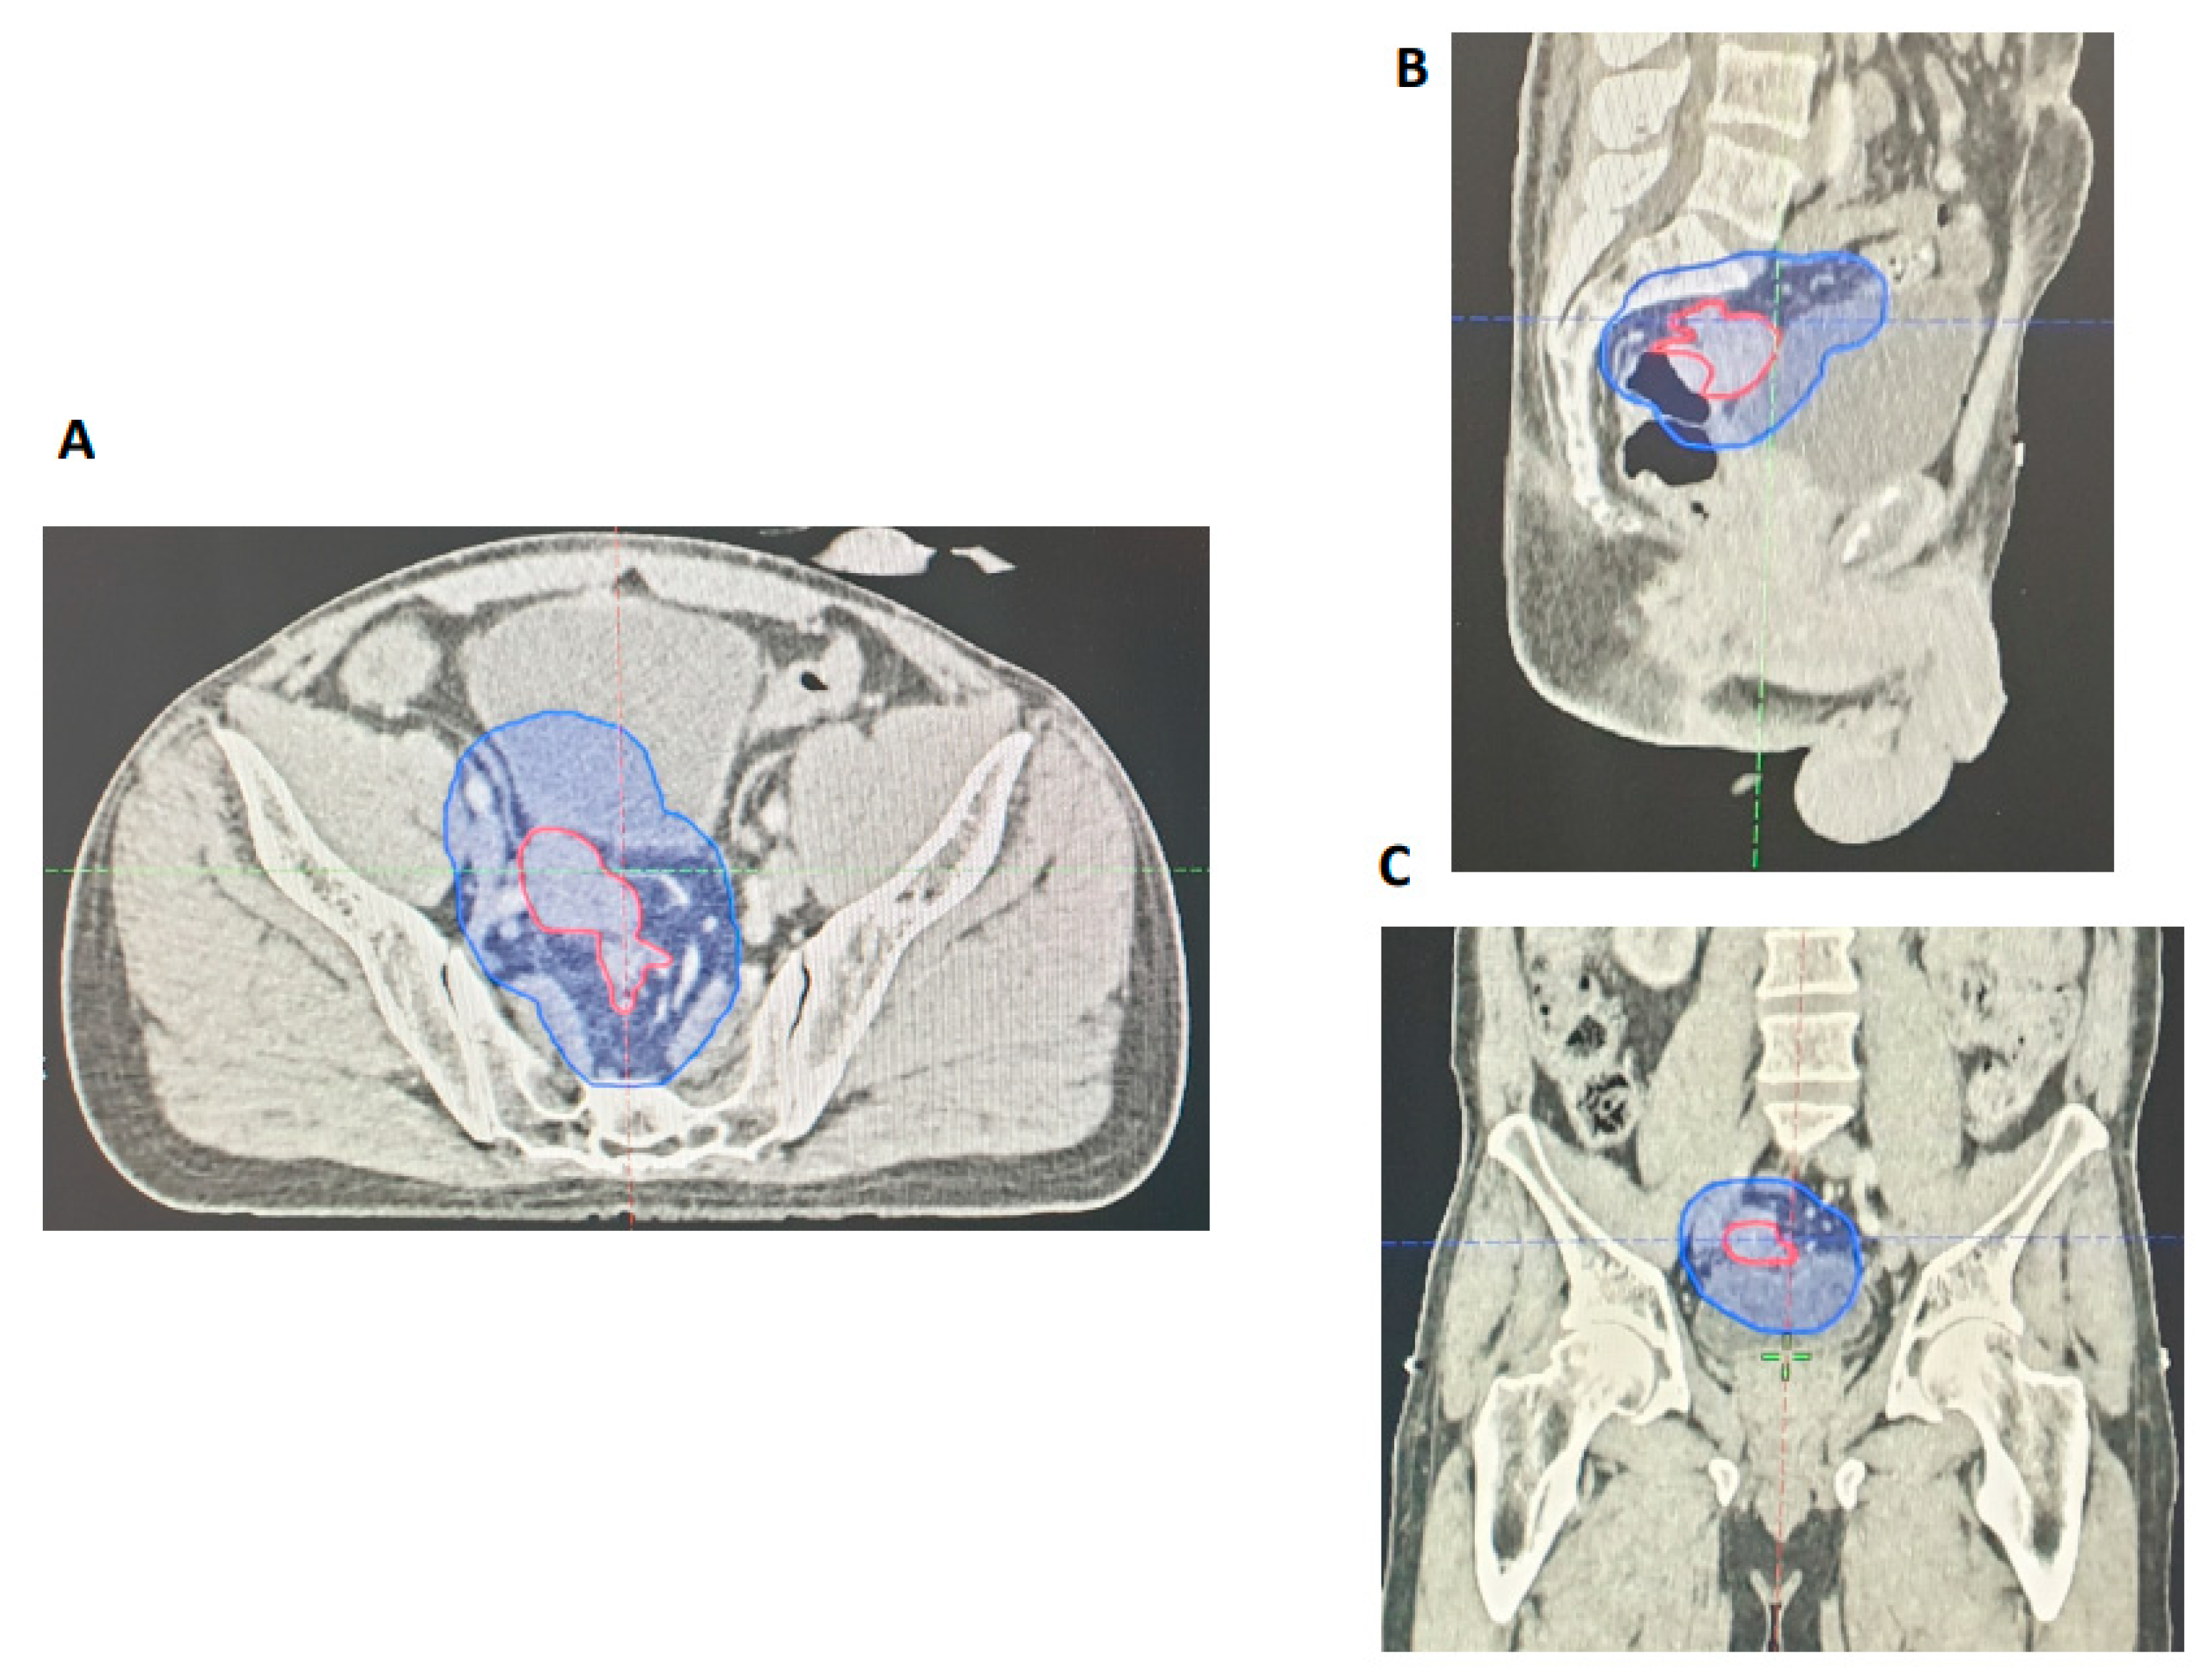

3.2.2. Retrospective Assessment of GTV Delineation by GI Radiologists